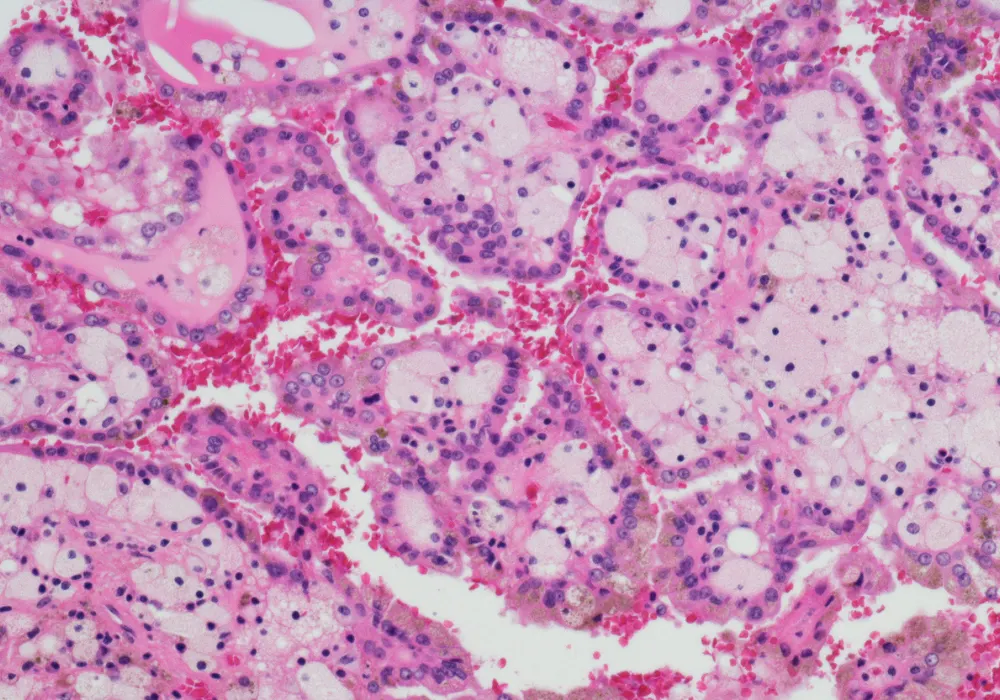

Clear cell renal cell carcinoma (ccRCC) represents the most common subtype of kidney cancer and remains a clinical challenge due to its variable progression and risk of recurrence. Despite early detection and treatment through surgery or ablation, up to one-third of cases may relapse, necessitating accurate risk assessment prior to treatment. The SSIGN score, incorporating tumour stage, size, grade and necrosis, is an established postoperative tool to stratify patient prognosis. However, its reliance on pathological data limits its utility in preoperative planning. To address this gap, researchers have developed an interpretable CT-based vision transformer (ViT) model capable of predicting the SSIGN score and clinical outcomes in ccRCC patients using preoperative imaging alone.